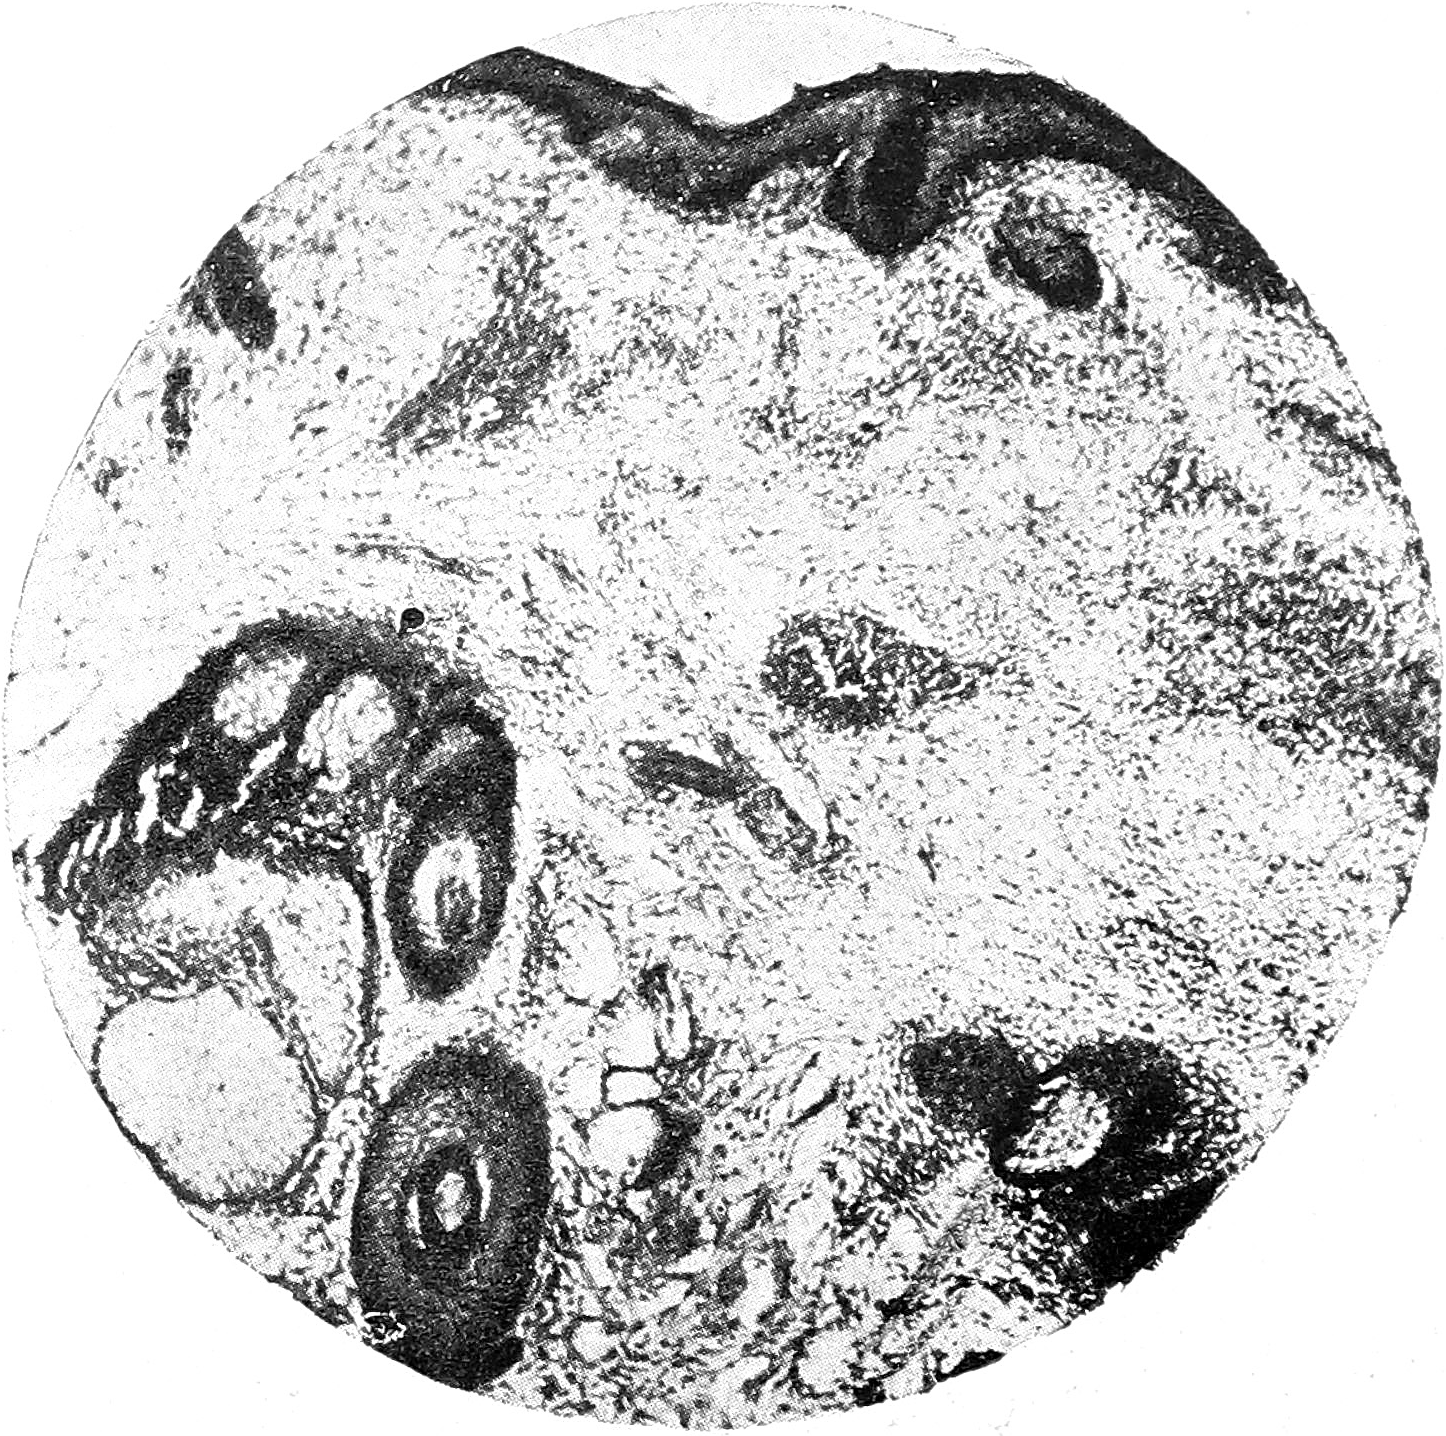

Биописия № 1 (с волосистой части головы) (рис. 1). Роговой слой почти нормальной толщины, местами разволокнен или слущен, изредка местами имеется незначительно выраженный паракератоз. Расширенные устья сально-волосяных фолликулов заполнены роговыми массами. Зернистый слой большею частью выражен хорошо, лишь в очагах парактератоза выражен неясно. В rete Malpygii мутное набухание эпителиальных клеток, незначительная вакуолизация и интерстициальное воспаление. Граница между эпидермисом и дермой невезде отчетливо выражена. По всей дерме, в сосочковом и подсосочковом слое, имеется диффузная, не очень густая инфильтрация; этот инфильтрат густо группируется вокруг сосудов, которые представляются значительно расширенными. Особенно расширены сосуды поверхностной сети дермы, в которых можно отметить и набухание эндотелия. Некоторые сосуды наполнены кровью. Местами имеются значительные кровоизлияния в дерму, иногда захватывающие значительную часть препарата. Наибольшие изменения мы находим в сально-волосяных фолликулах и потовых железах. В глубоких частях дермы и даже отчасти в подкожной жировой клетчатке встречаются также очаги инфильтрата, причем очаги эти почти всегда локализуются около тех или иных придатков кожи, преимущественно вокруг сально-волосяных мешечков у устьев их, у потовых желез, и mm. erectores pilorum. Процесс не ограничивается, однако, лишь тем, что инфильтрат окружает все придатки кожи,—-инфильтрат этот проникает и в самые волосяные мешечки и сальные железы (рис. 2). Там, где имеется диффузный и достаточно мощный инфильтрат, там коллагенная и эластическая ткани отсутствуют; эластическая ткань сохранена только в промежутках между очагами инфильтрата. Пронизанные инфильтратом придатки кожи находятся в стадии расплавления. Инфильтрат состоит, главным образом, из лимфоцитов, однако встречаются и др. элементы, как, например, плазматические клетки, фибробласты и тучные клетки.

Рис. 1.